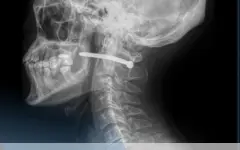

01:28 22.10.2025 Общество В Петропавловске мужчина случайно выстрелил себе гвоздем в шею Житель Петропавловска случайно выстрелил себе в шею гвоздём из пневмопистолета во время ремонта, передает ИА «NewTimes.kz». Петропавловскбольницатравмаврач Читать